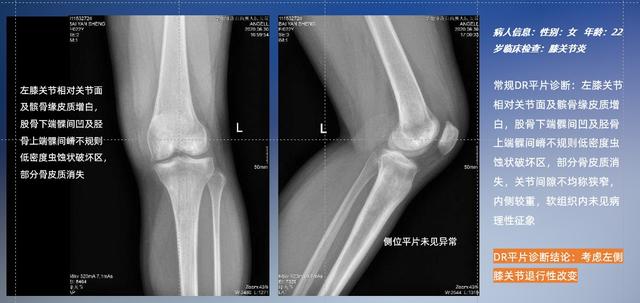

普通平片扫描与WR-3D扫描前后诊断结果对比

与此同时,数字化X线摄影技术相较于CTMRI来说,能快速获取真实、直观、满足临床需要的影像。DR的图像具有图像层次丰富、空间分辨力高、影像边缘锐利清晰、密度分辨力高级细微结构表现出色等特点,针对膝关节解剖结构数字化X线摄影技术应用价值很高,尤其是是对骨小梁与骨皮质的显示非常清楚。在负重位状态下,数字化X线三维摄影扫描与重建,能够更好的呈现受检者关节受力改变的状态。ty8天游平台登录科技创新的WR-3D动态三维数字化X线摄影技术,通过数字化X线摄影完成三维扫描并重建三维影像信息,包括MPR多平面重建、MIP重建以及VR绘制。扫描时间短,剂量相较于CT设备大幅缩减,同时成本更低,在临床诊断以及医疗方案制定中具有极大的价值意义。相较于普通平片下的负重位扫描,负重位动态三维扫描摄影技术能够避免二维状态下的组织结构重叠、密度分辨率不足、组织解剖结构难以分辨等问题,WR-3D支持多角度的动态三维摄影观察,能全面的呈现被检查部位在多个角度下三维影像信息,极大的减少了二维负重位检查的漏诊率。